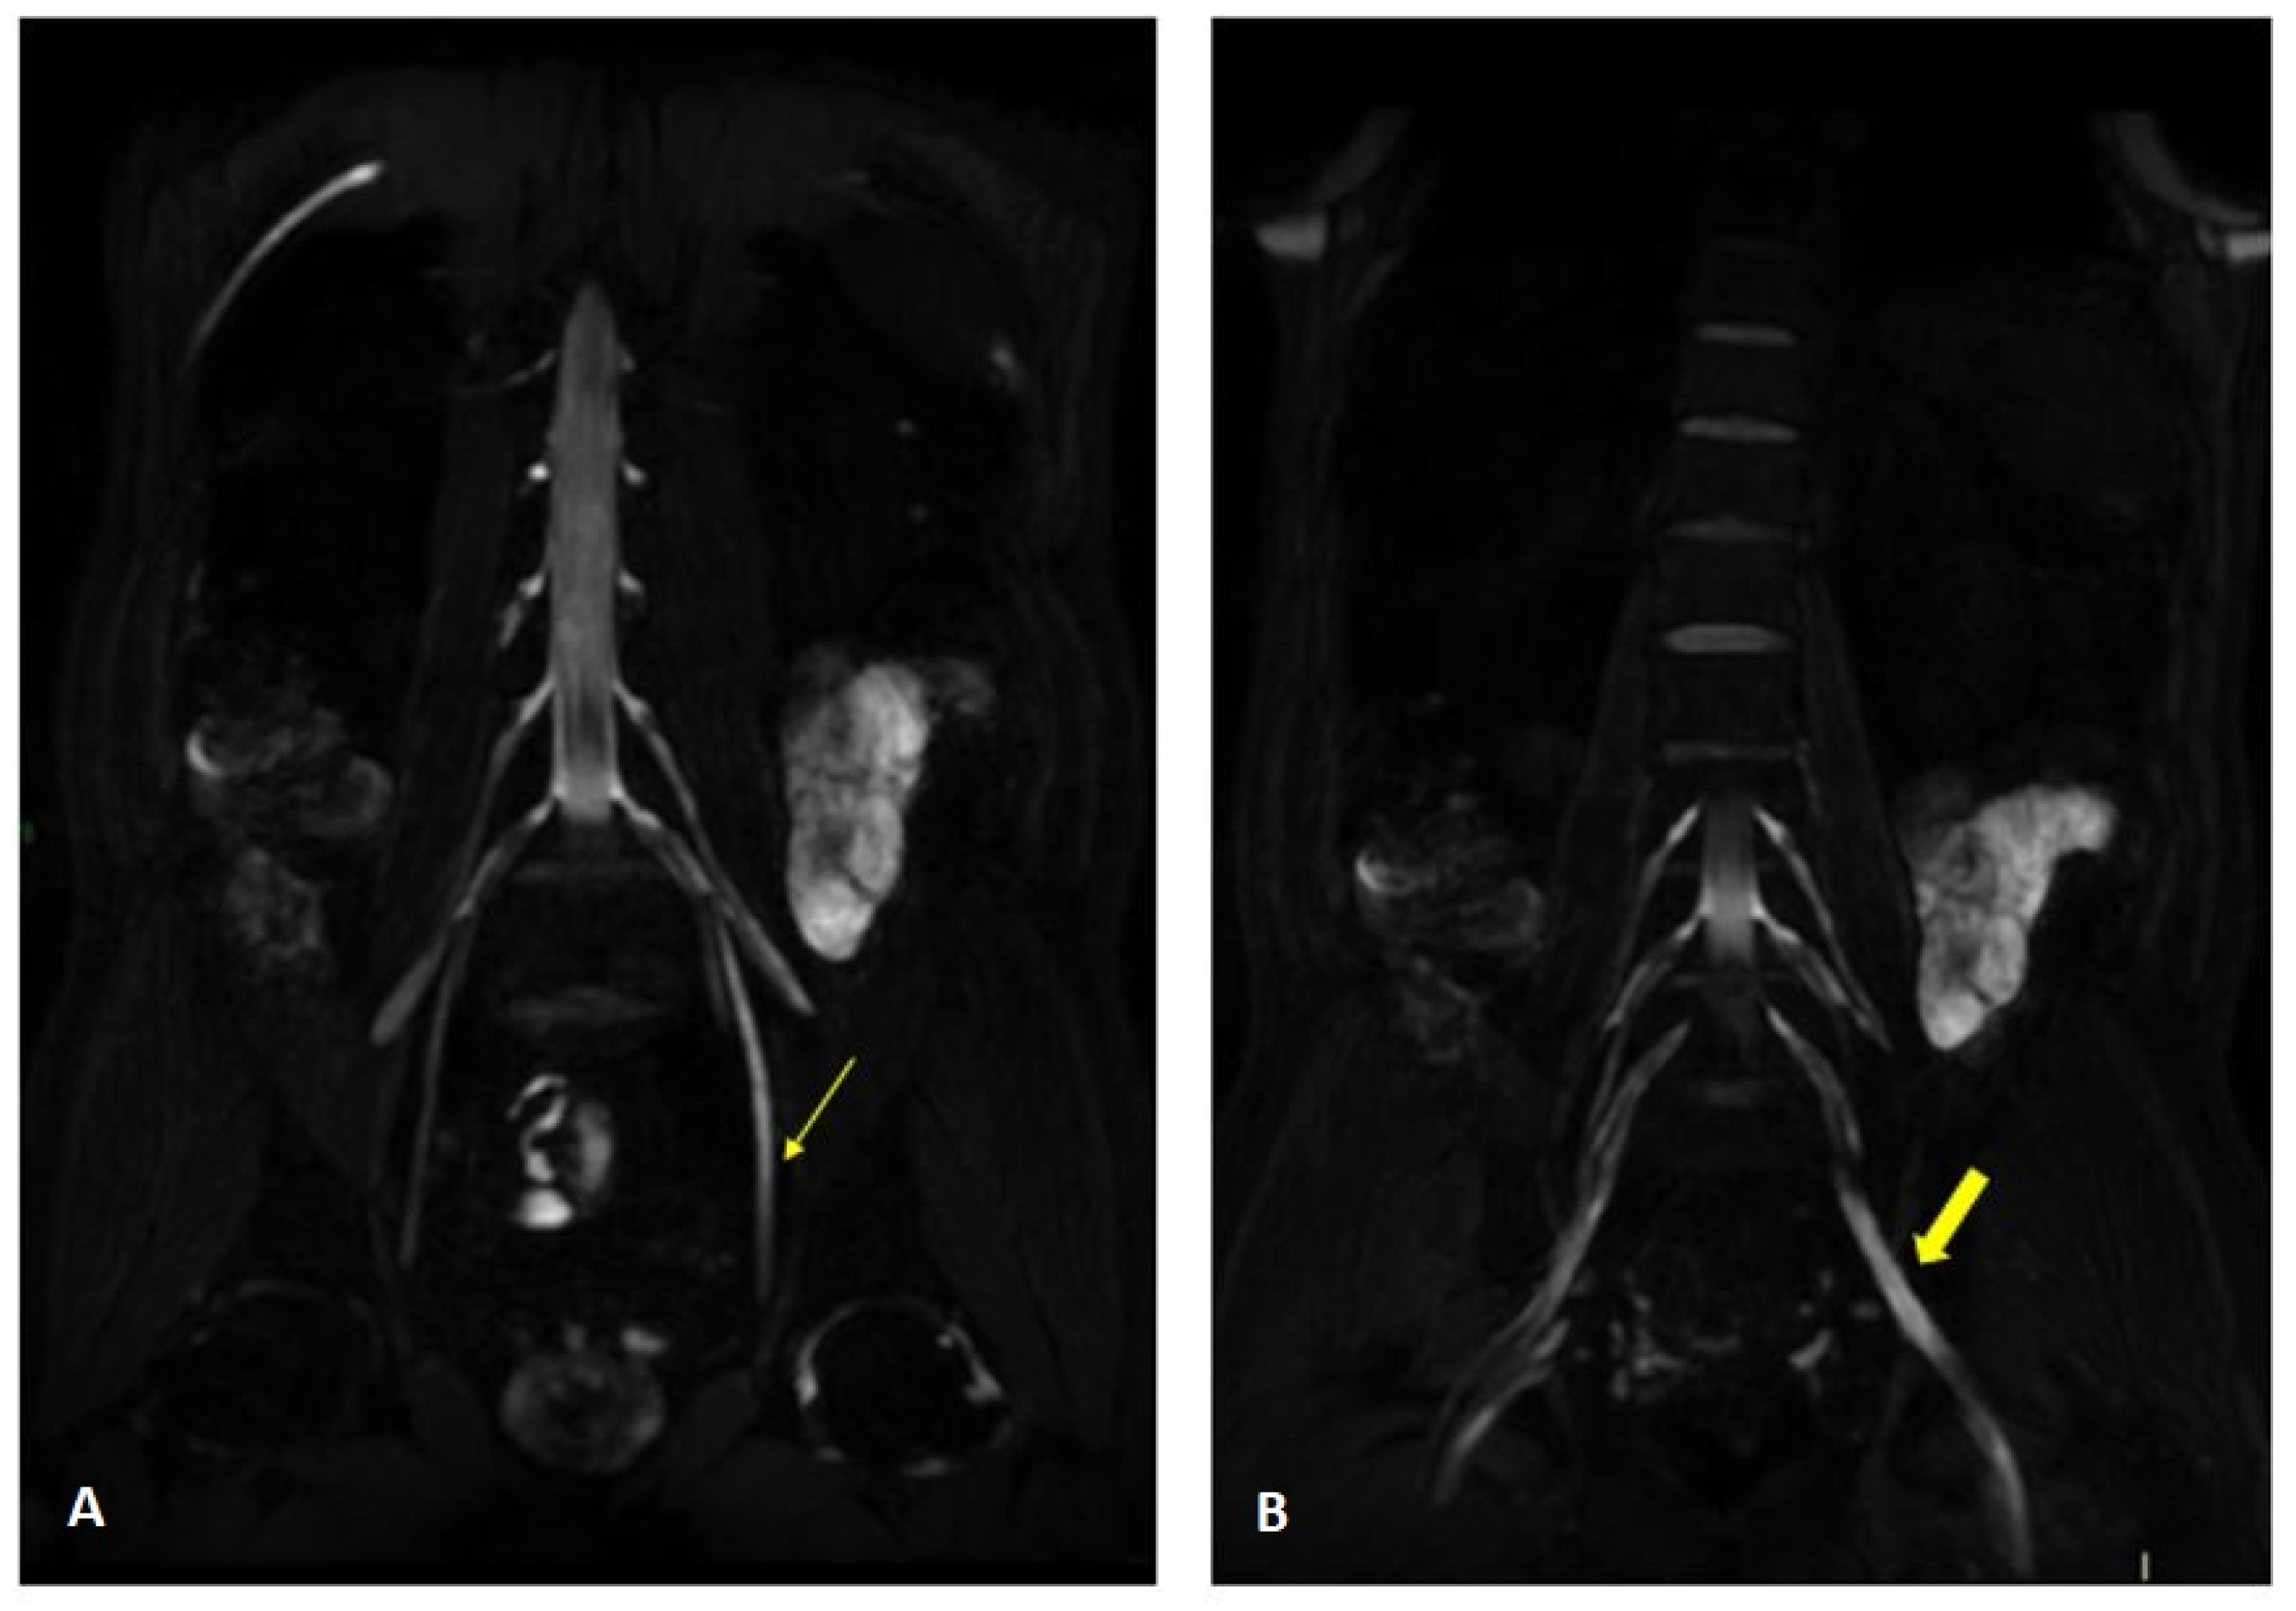

Figure 7.

Axial 2D MR of sciatic nerve; on the left are the T1w images and on the right are the T2 STIR images. Bilateral and symmetrical sciatic nerve T2 enlargement and fascicular hyperintensity at the level of the gluteal region (thin arrows (B); CSA of sciatic nerve of 103 mm2 on the right; 90.1 mm2 on the left) and at the mid-thigh (thin arrows in (D,F)). Mixed, acute and chronic denervation of the muscles of the anterolateral compartment of the thigh with denervation edema (hyperintensity in STIR, arrowheads in (D,F)) and fat replacement (thick arrows in (C,E)). Mainly chronic denervation of the gluteal muscles (hyperintensity in T1w, thick arrows in (A)).